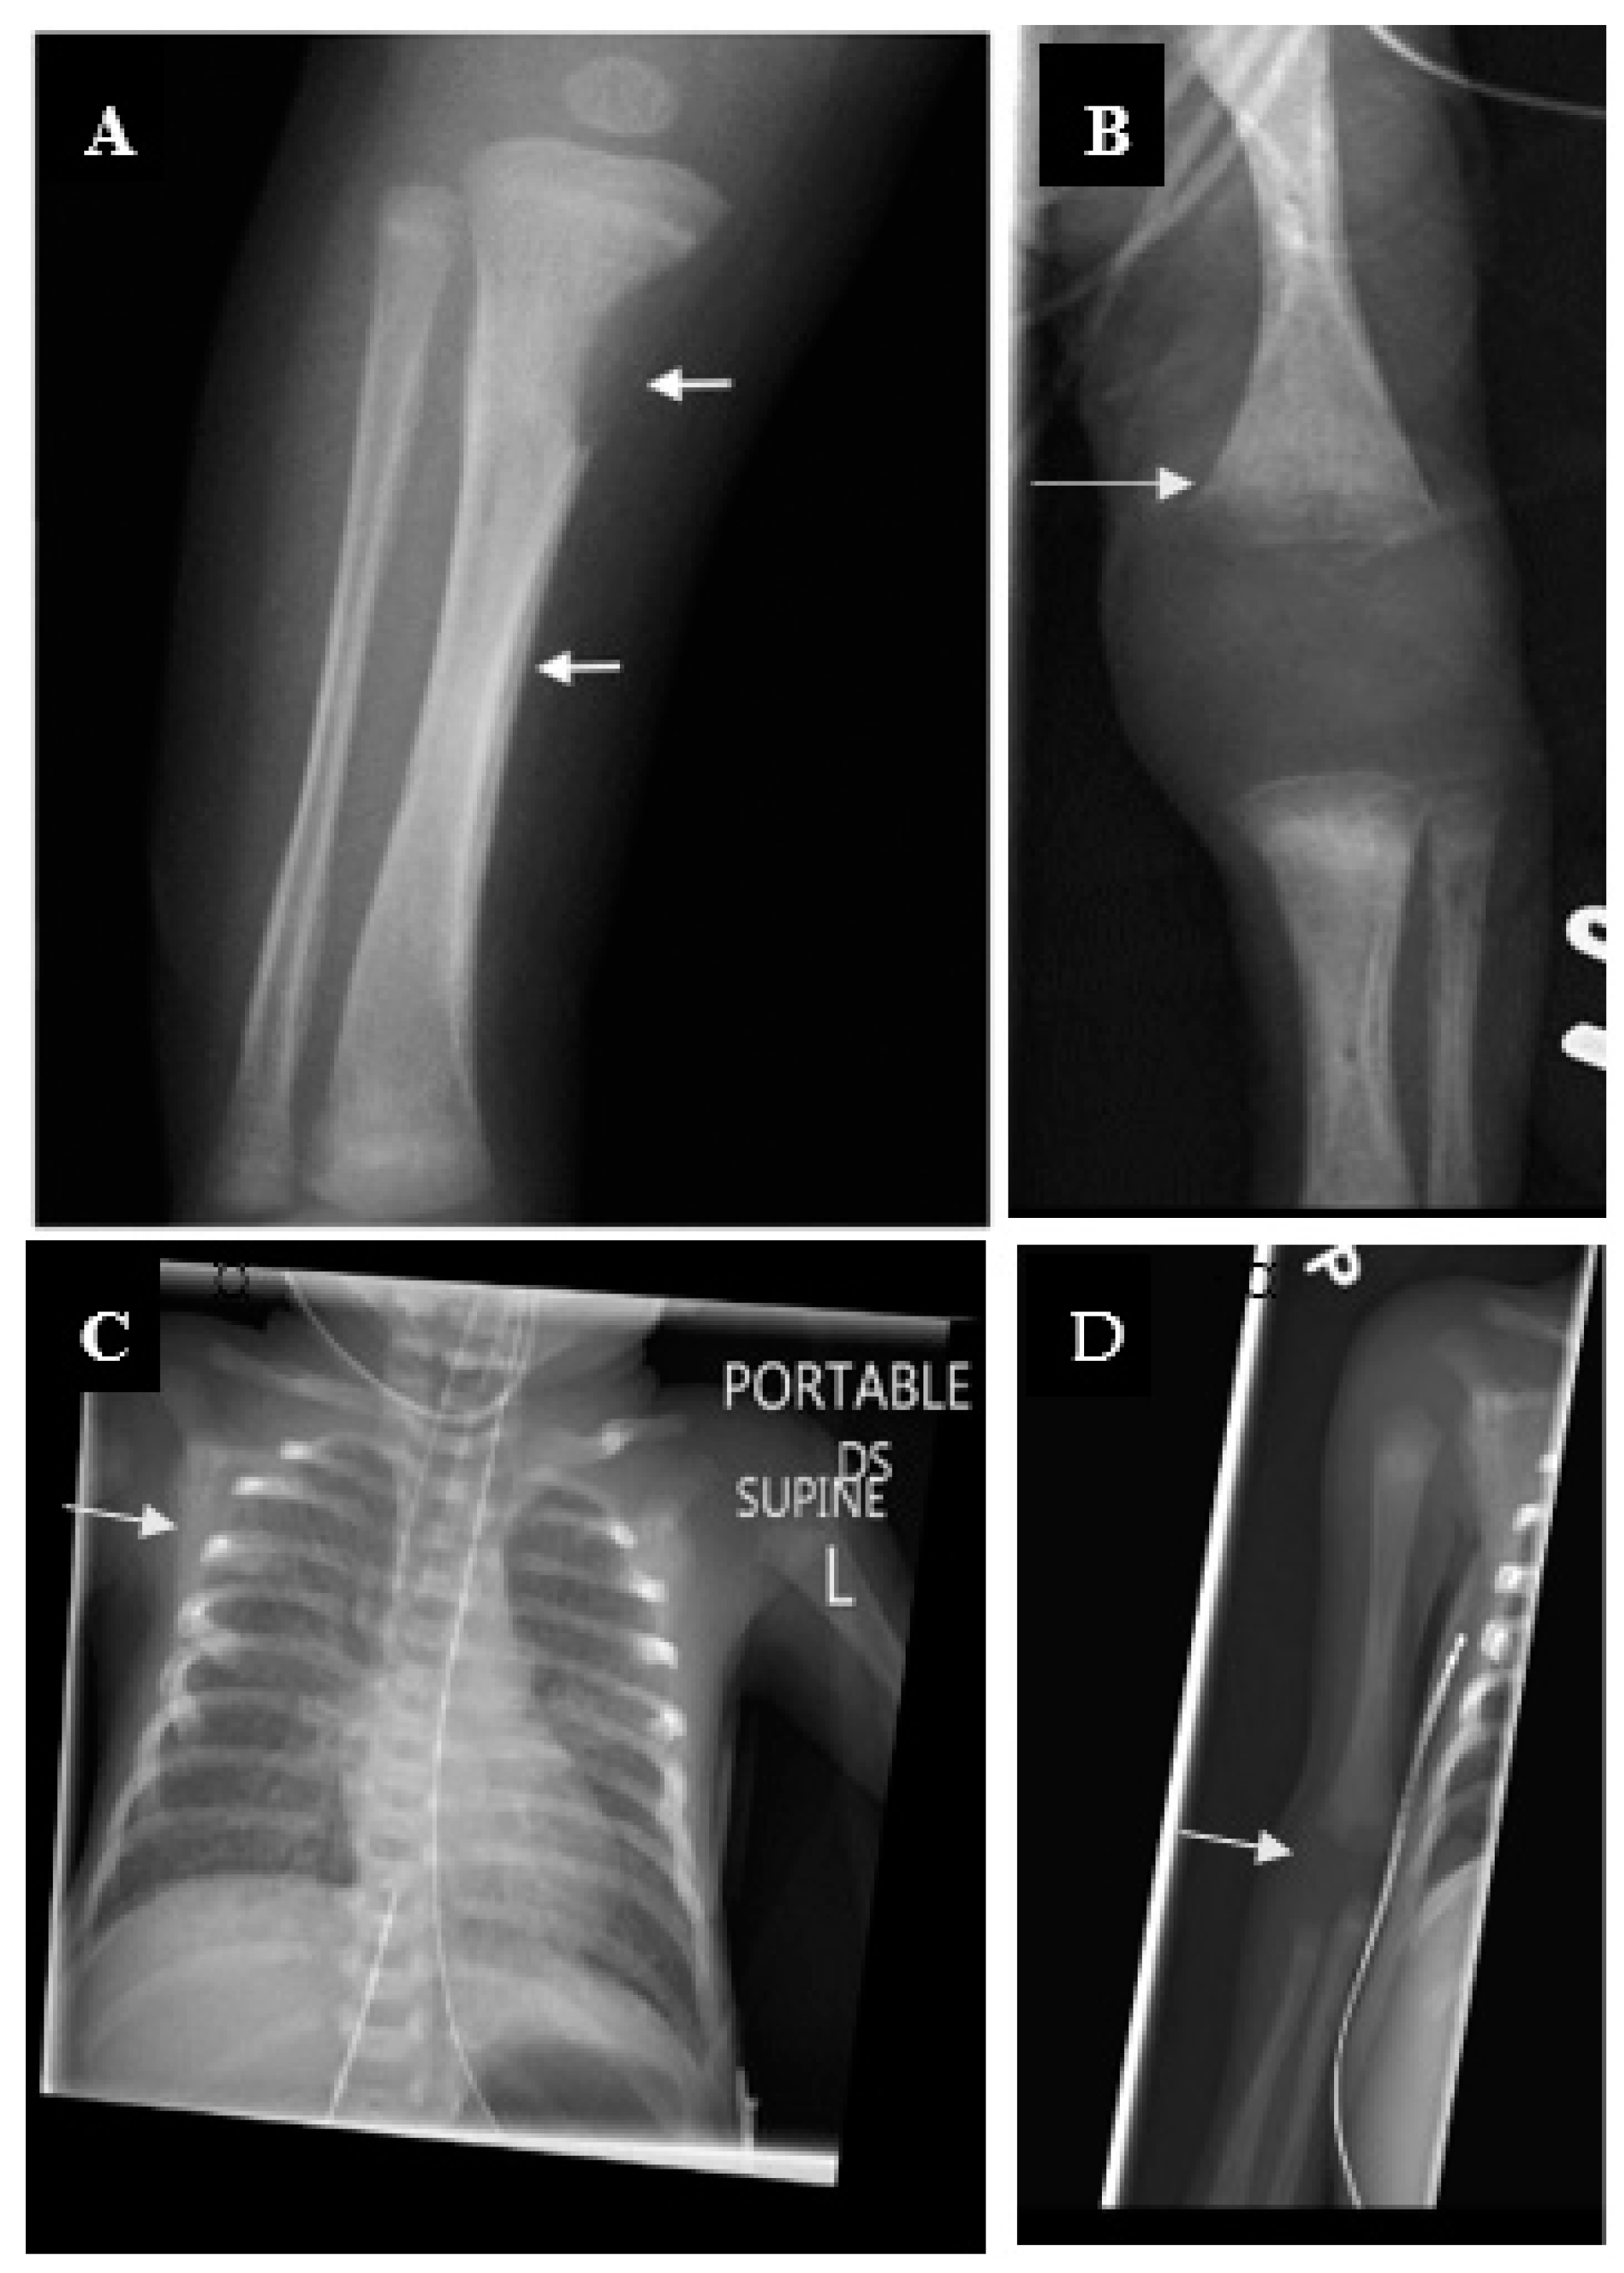

| Long bone lesions (Wimberger sign in tibial protuberance) | Clavicle (sternal end) hypertrophy (Higoumenakis’ sign) | ||

| Periostitis (pseudoparalysis) | Clutton’s joints (knees) | ||